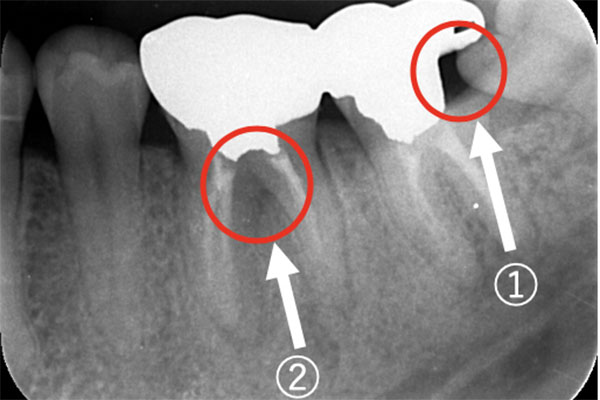

【担当医師所見】

左下奥歯は親知らずが原因でクラウン(かぶせ物)の下まで虫歯になっています。 またその手前の歯は根中央部に大きな透過像(黒い像)が見られます。クラウン除去後、マイクロスコープ下で確認したところ中央部は亀裂が入り保存不可能な状態になっており抜歯となりました。

また右上6番にも大きな透過像があり虫歯となっていることがわかります。

①親知らず手前の歯はクラウン(白い不透過像)直下に大きな透過像(黒い部分)が見られこのような場合は抜歯になる確率が高いです。

②歯根分岐部(中央部)に及ぶ歯周炎ー根尖性歯周炎の原因はクラウン除去後にマイクロスコープ下にて破折線を確認したため抜歯となりました。